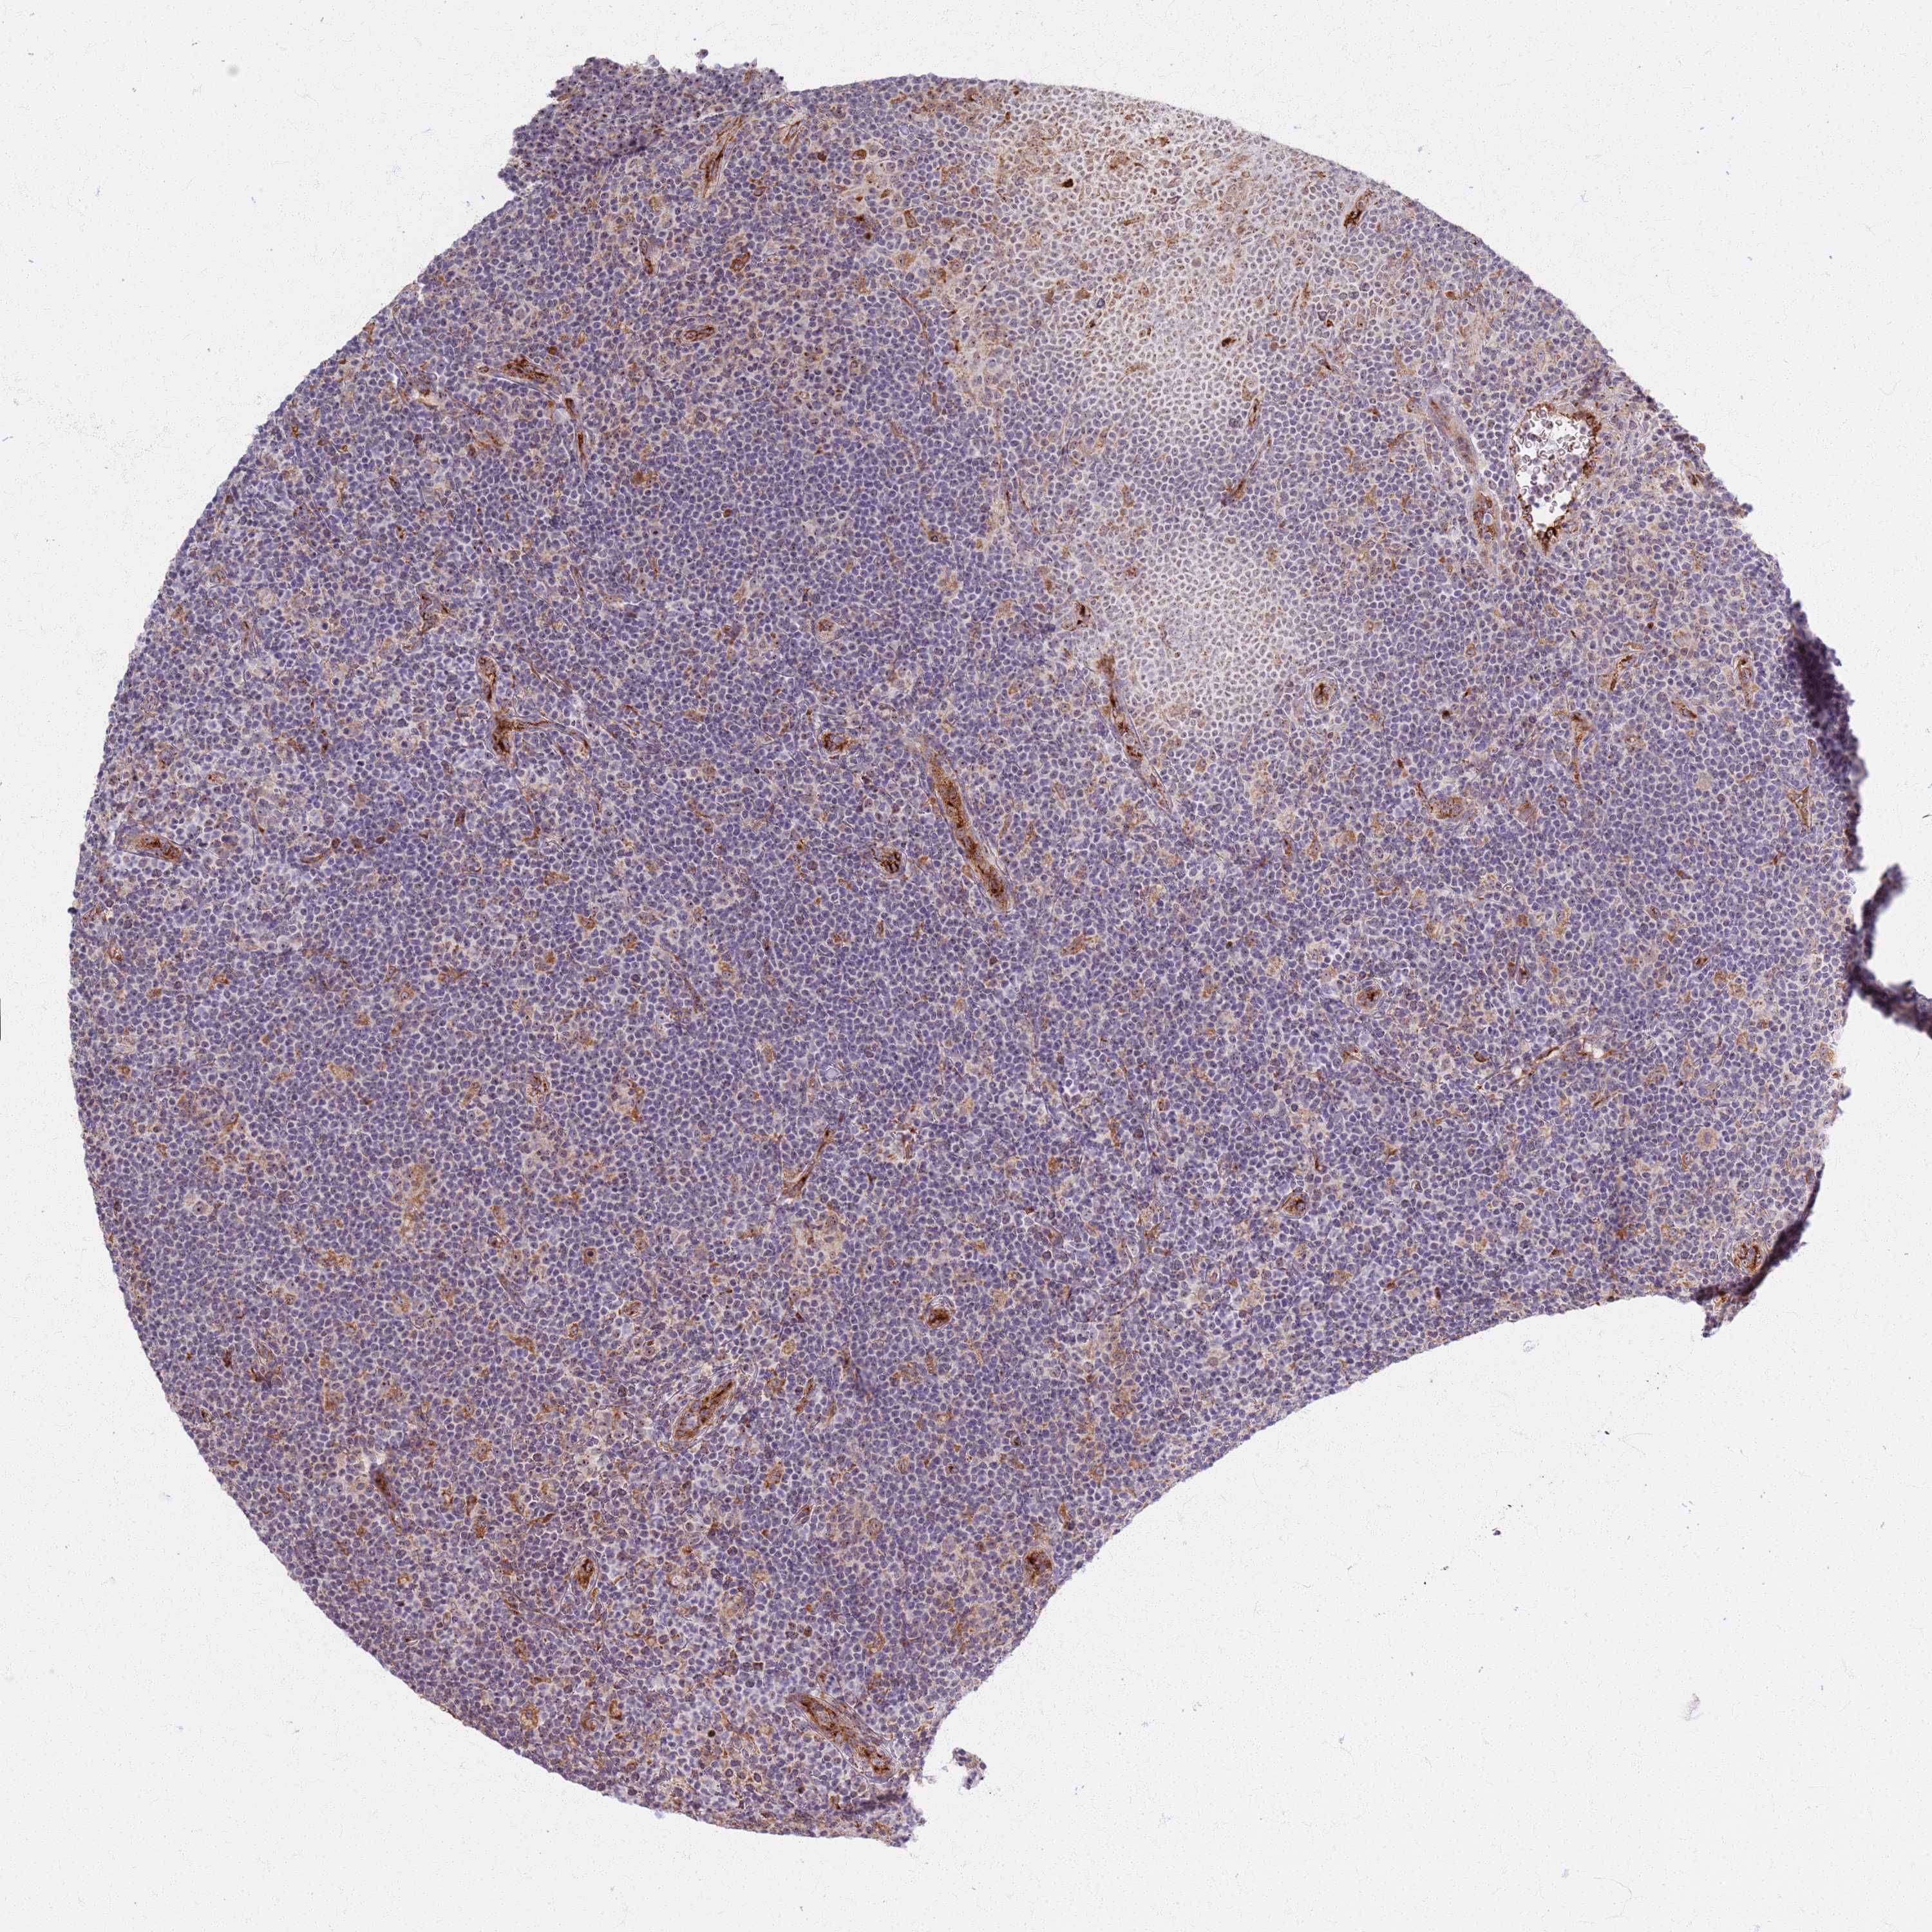

CANCER LYMPHOMA Show tissue menu

LYMPHOMA - Protein expressioni

A mouse-over function shows sample information and annotation data. Click on an image to view it in a full screen mode. Samples can be filtered based on level of antibody staining by selecting one or several of the following categories: high, medium, low and not detected. The assay and annotation is described here.

Each image is clickable and will lead to virtual microscopy that enables deeper exploration of all samples and also displays staining intensity scores, fraction scores and subcellular localization as well as patient and tissue information for each sample.

Antibody HPA043110

Antibody HPA043574

Hodgkin's disease, NOS

Malignant lymphoma, non-Hodgkin's type, High grade

Malignant lymphoma, non-Hodgkin's type, Low grade